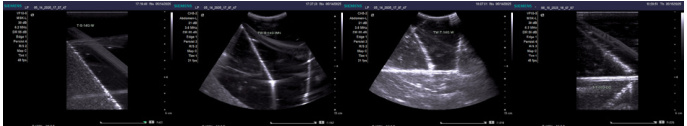

(三)实验结果与分析

1、实验结果

水介质环境下,所有规格穿刺针均表现出最佳显影效果。这得益于水分子结构的均一性,超声波传播过程中仅产生简单的反射,形成清晰图像。16G 至 22G 针具均能明确辨识,且浅表探头与腹部探头表现相当。这一结果为建立基础参照标准提供了依据;TPE 软胶体模作为模拟组织,表现出较好的显影效果。虽然其声学特性略复杂于水,但由于成分相对均匀,不同规格穿刺针仍能保持较好的可视性。值得注意的是,22G(Φ0.7mm) 细针的显影质量已出现轻微下降,提示针径大小仍是影响可视性的关键因素;生物组织环境中,显影效果显著降低。猪肉组织因含有皮肤、肌肉、脂肪等多种成分,超声波传播时产生复杂的反射、折射和吸收现象。猪肝组织则因存在微小气孔,进一步干扰了超声成像。在这些环境中,18G 以下细针的显影已难以满足精准操作需求。

② . 探头类型的影响分析:

对比浅表探头(VF10-5) 和腹部探头(CH5-2) 的表现,研究发现两者在显影效果上无显著差异。这一结果表明,对于穿刺针可视性而言,探头的选择可能不如介质特性影响显著。然而,这一结论需要在更多样化的实验条件下进一步验证。